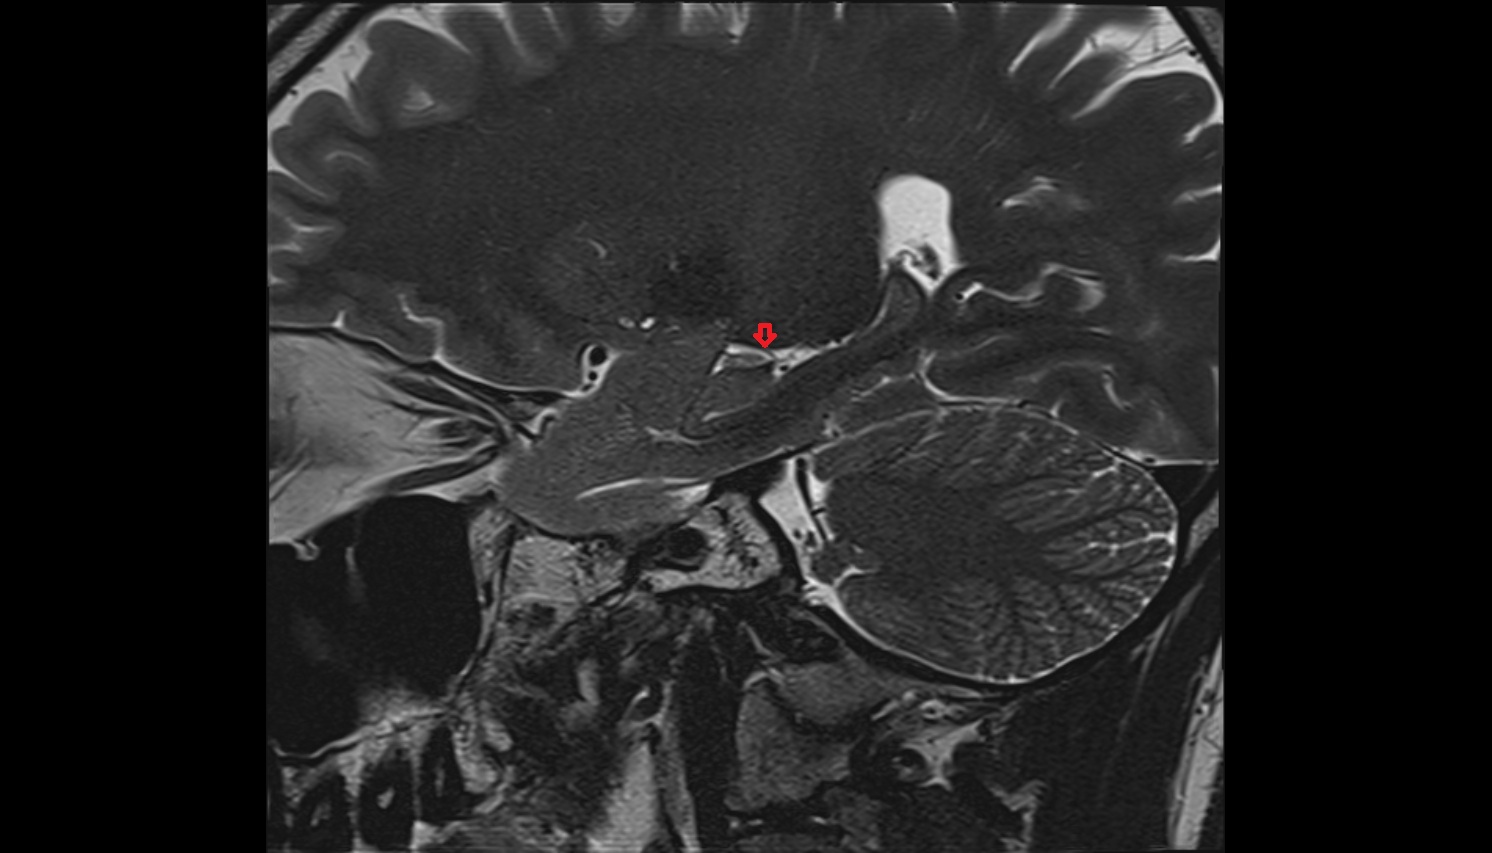

- Temporomandibular joint

- Articular disc of temporomandibular joint

- Mandibular condyle

- Mandibular fossa